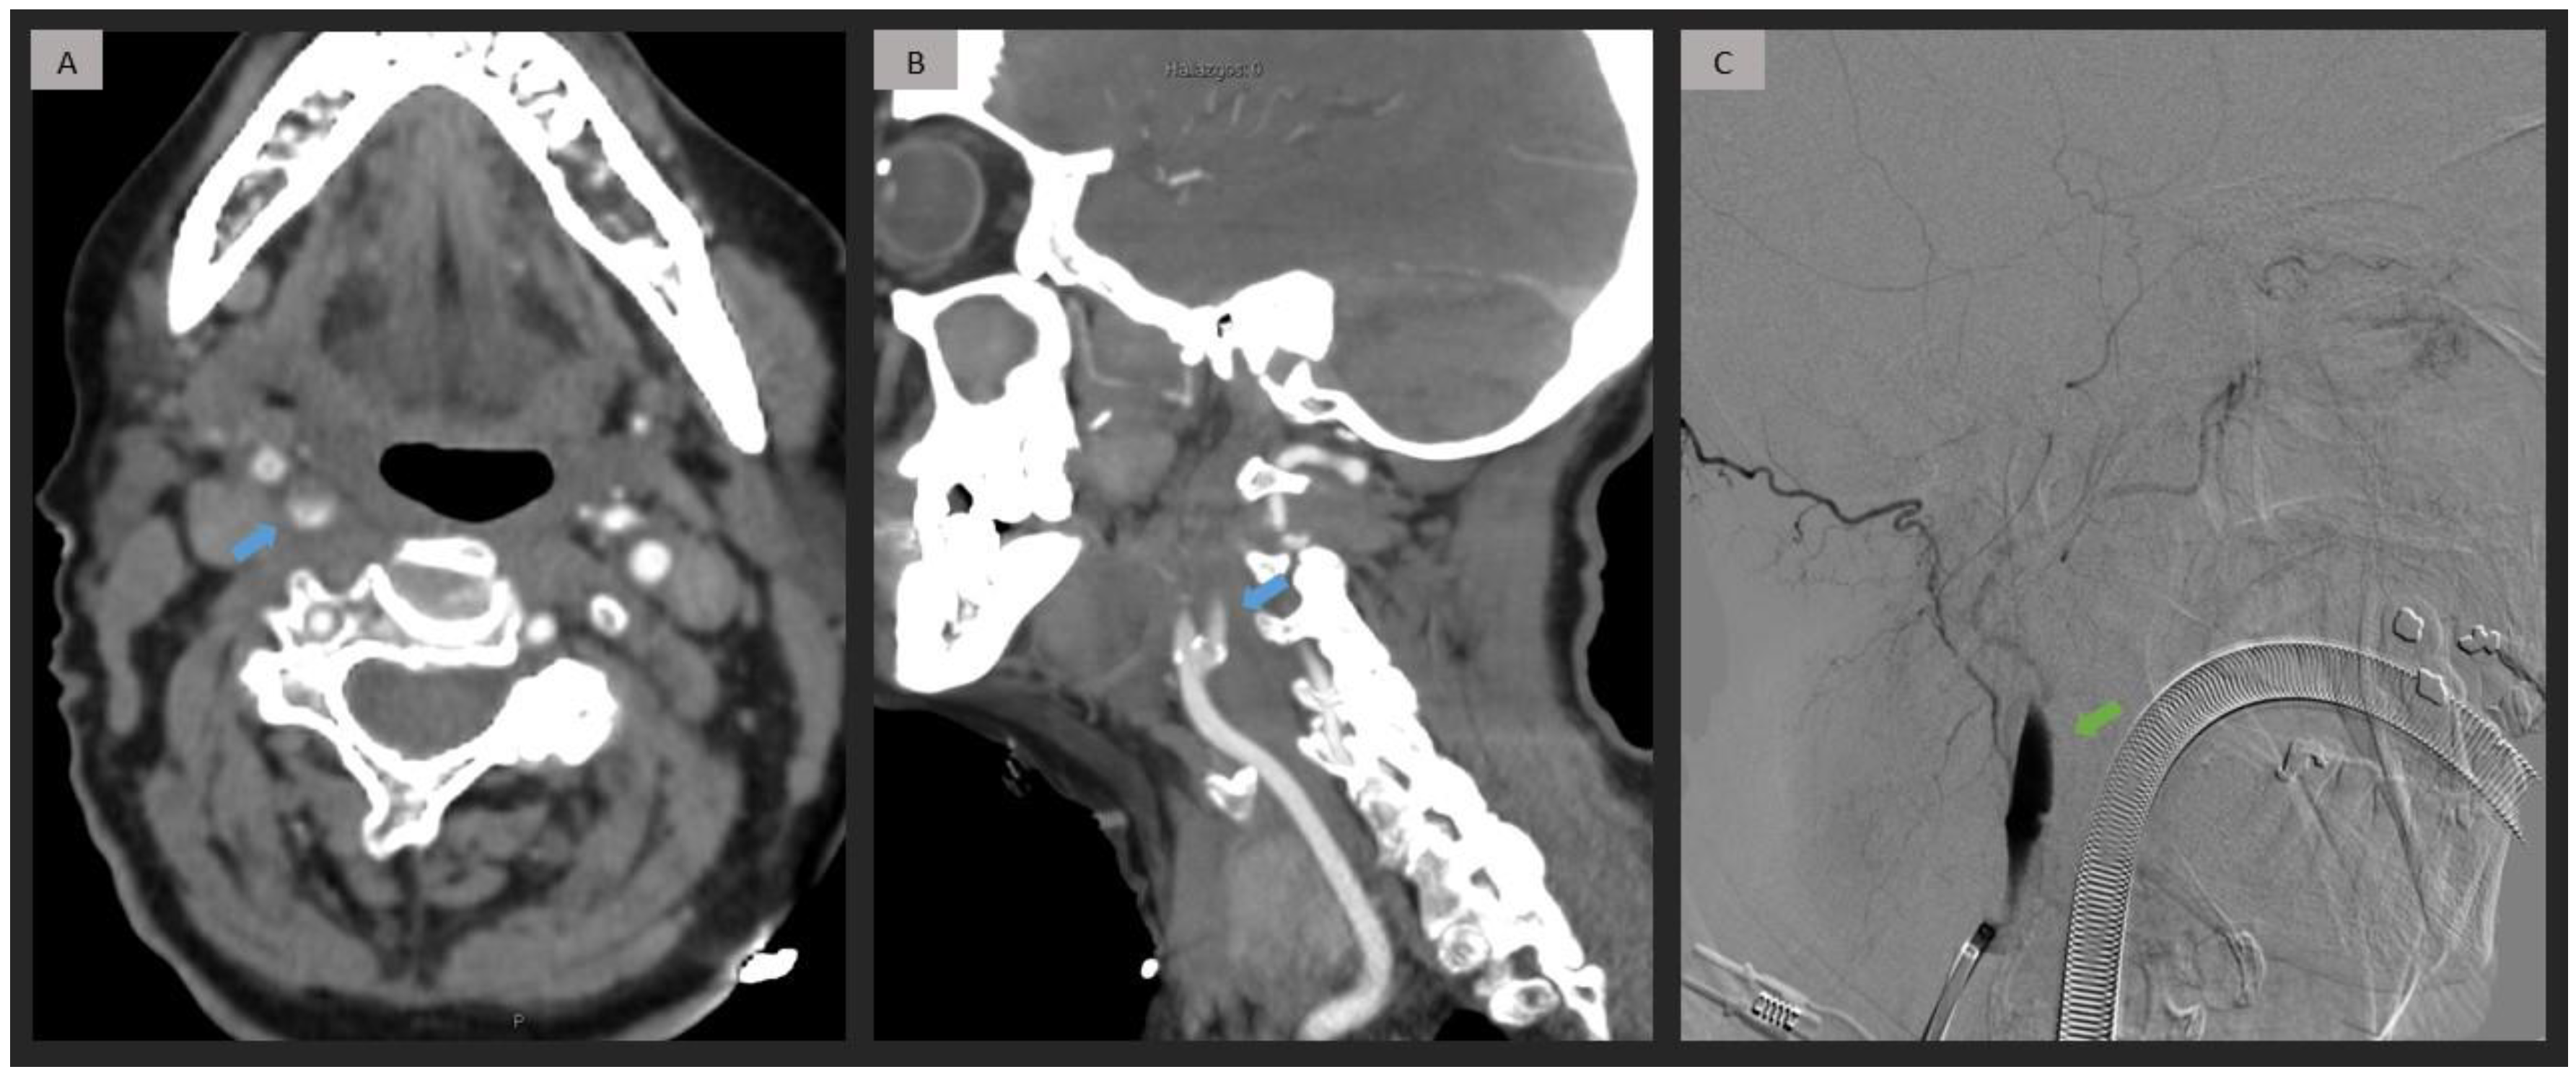

Figure 1.

Right extracranial ICA occlusion caused by thromboembolism in a patient with a history of atrial fibrillation. CTA (A,B) shows an extracranial short progressive contrast decline (blue arrow), with calcifications in the origin of the ICA, proximal to the occlusion site. DSA (C) confirms a cervical ICA occlusion (green arrow) due to thromboembolism, without carotid mural lesions. ICA = internal carotid artery; CTA = computed tomography angiography; DSA = digital subtraction angiography.